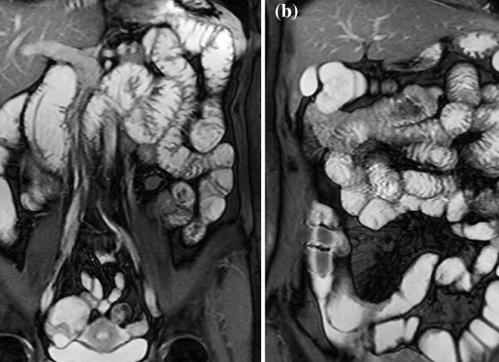

Наиболее достоверным и распространенным признаком болезни Крона является неравномерное утолщение кишечной стенки. Кроме того, выявляются такие признаки, как расслоение стенки кишки, сегментарное поражение и продольные глубокие язвы. Благодаря данной диагностической методике имеется возможность обнаружения воспалительных изменений брыжейки и расстройств кровоснабжения.

Для каждой формы болезни Крона характерно увеличение размеров лимфатических узлов на всей протяженности брыжейки тонкой кишки. Кроме того, на МРТ снимках отчетливо видны отечные ткани, которые окружают кишечник. Стенки воспаленной кишки склонны накапливать контрастное вещество.